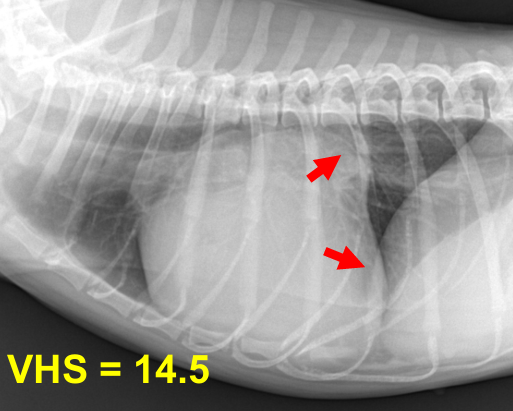

2기 (Moderate)

기존 소견 동일하게,

1) 심장 커짐

Left auricle 확장, cranial/caudal waist 소실, Globoid heart, Cardiomegaly

+ Sternal contact 매우 증가

2) 기관 영향

Tracheal elevation, bronchus compression

Static collapse로 발전